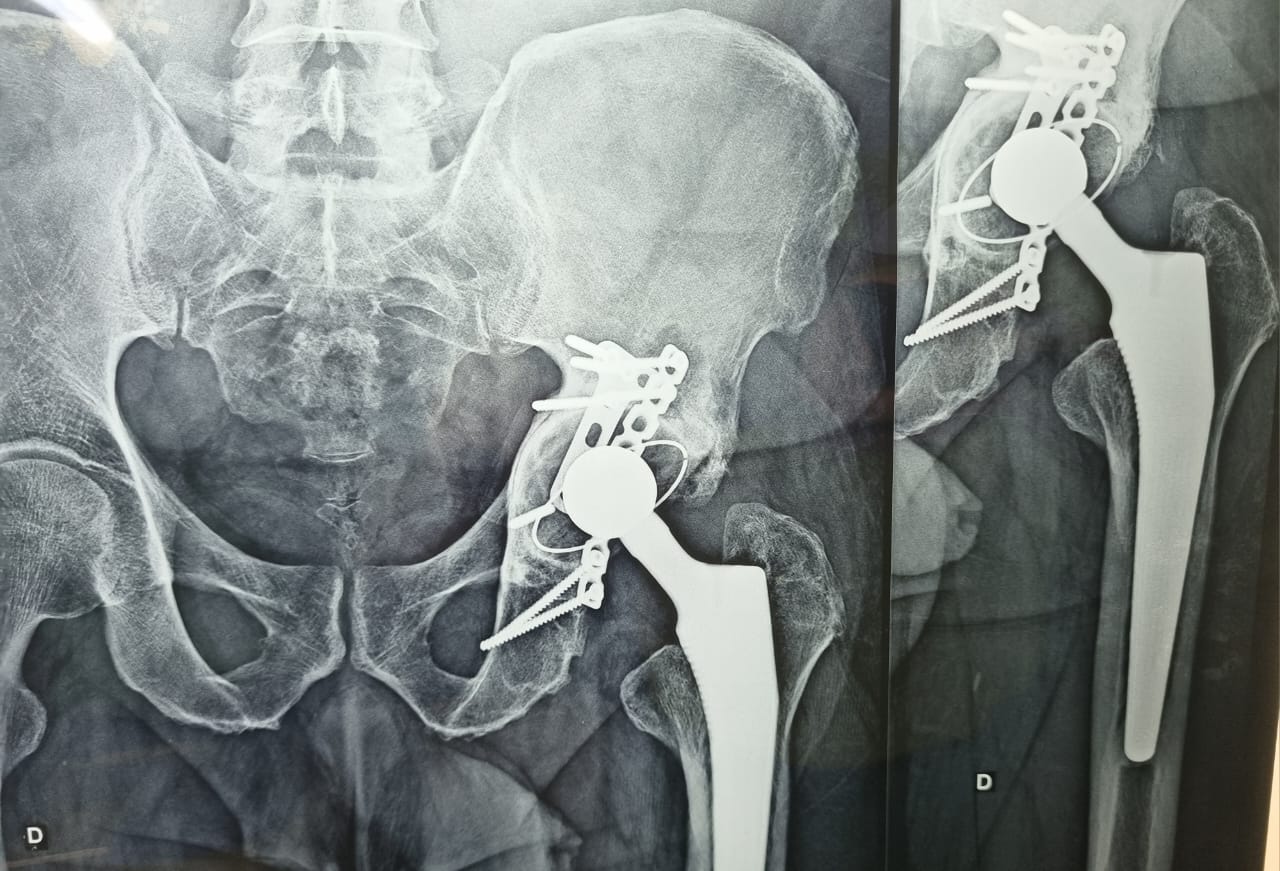

• Fraturas do Anel Pélvico;

• Próteses de Quadril (Primárias  e Revisões);

• Cirurgia do Quadril;